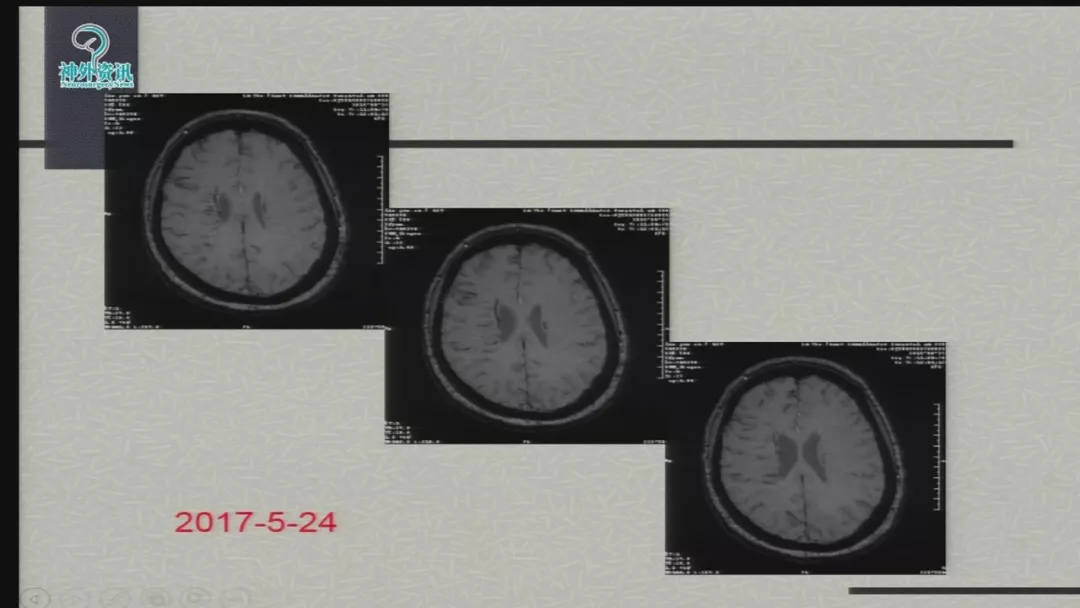

徐浩文:Neuroform EZ在ICAS治疗中的应用丨第七届全国介入医学工程大会精彩回顾

今天为大家分享的是由郑大一附院徐浩文教授在第七届全国介入医学工程大会上带来的“Neuroform EZ在ICAD治疗中的应用”精彩讲课视频和PPT,欢迎观看!(内容未经讲者审核,不当之处请与我们联系)